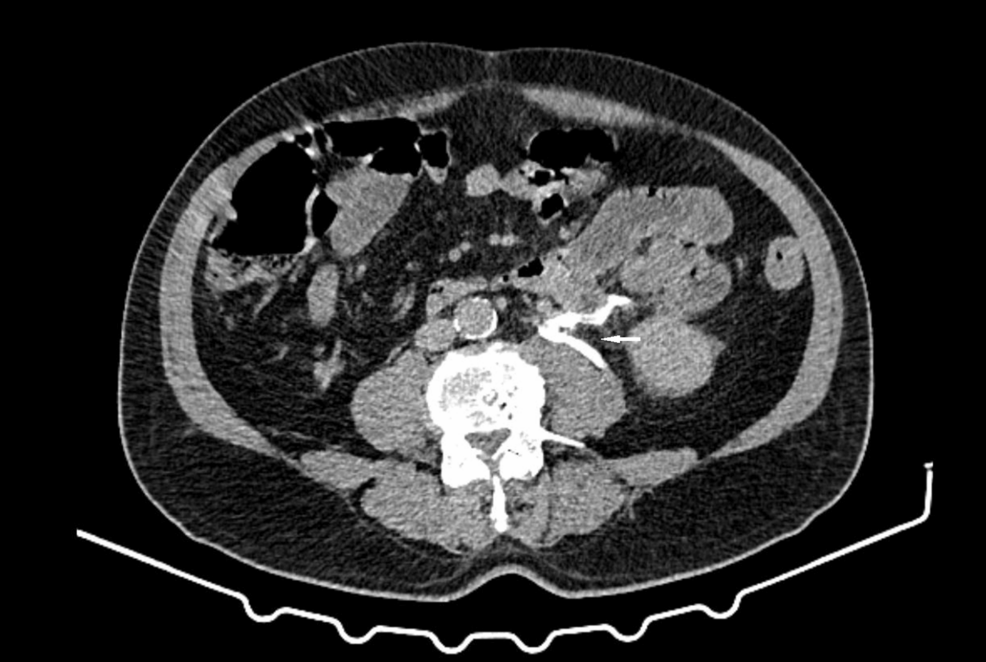

Computed tomography (CT) scans with intravenous contrast are the primary imaging modality for diagnosing ureteral rupture. The scan can reveal the location of the rupture, the presence of hydronephrosis, and any associated kidney stones. According to a case report published in Dergipark, spontaneous ureteral rupture is a rare urological emergency characterized by non-traumatic disruption of the ureteral wall [4]. The ability to quickly and accurately identify the rupture is critical for initiating appropriate treatment.

More frequently, ureteral rupture is linked to urolithiasis – the presence of kidney stones. A case study published in Clinical Practice & Cases in Emergency Medicine described a 55-year-old woman who presented with intense right lower abdominal pain, vomiting, and a single instance of hematuria (blood in the urine). Imaging revealed a 0.3-centimeter kidney stone in the upper right ureter, accompanied by hydronephrosis (swelling of the kidney due to urine backup) and ureteral rupture [2]. This case underscores how even relatively small stones can cause significant obstruction and lead to rupture.

Another case report detailed a 24-year-old female presenting with acute right flank pain, nausea, and vomiting caused by a 3 mm distal ureteric stone. Imaging revealed hydroureteronephrosis with urine extravasation, and immediate double-J stent placement successfully resolved the obstruction [5]. The prognosis for patients with spontaneous ureteral rupture is generally good with prompt diagnosis and treatment.